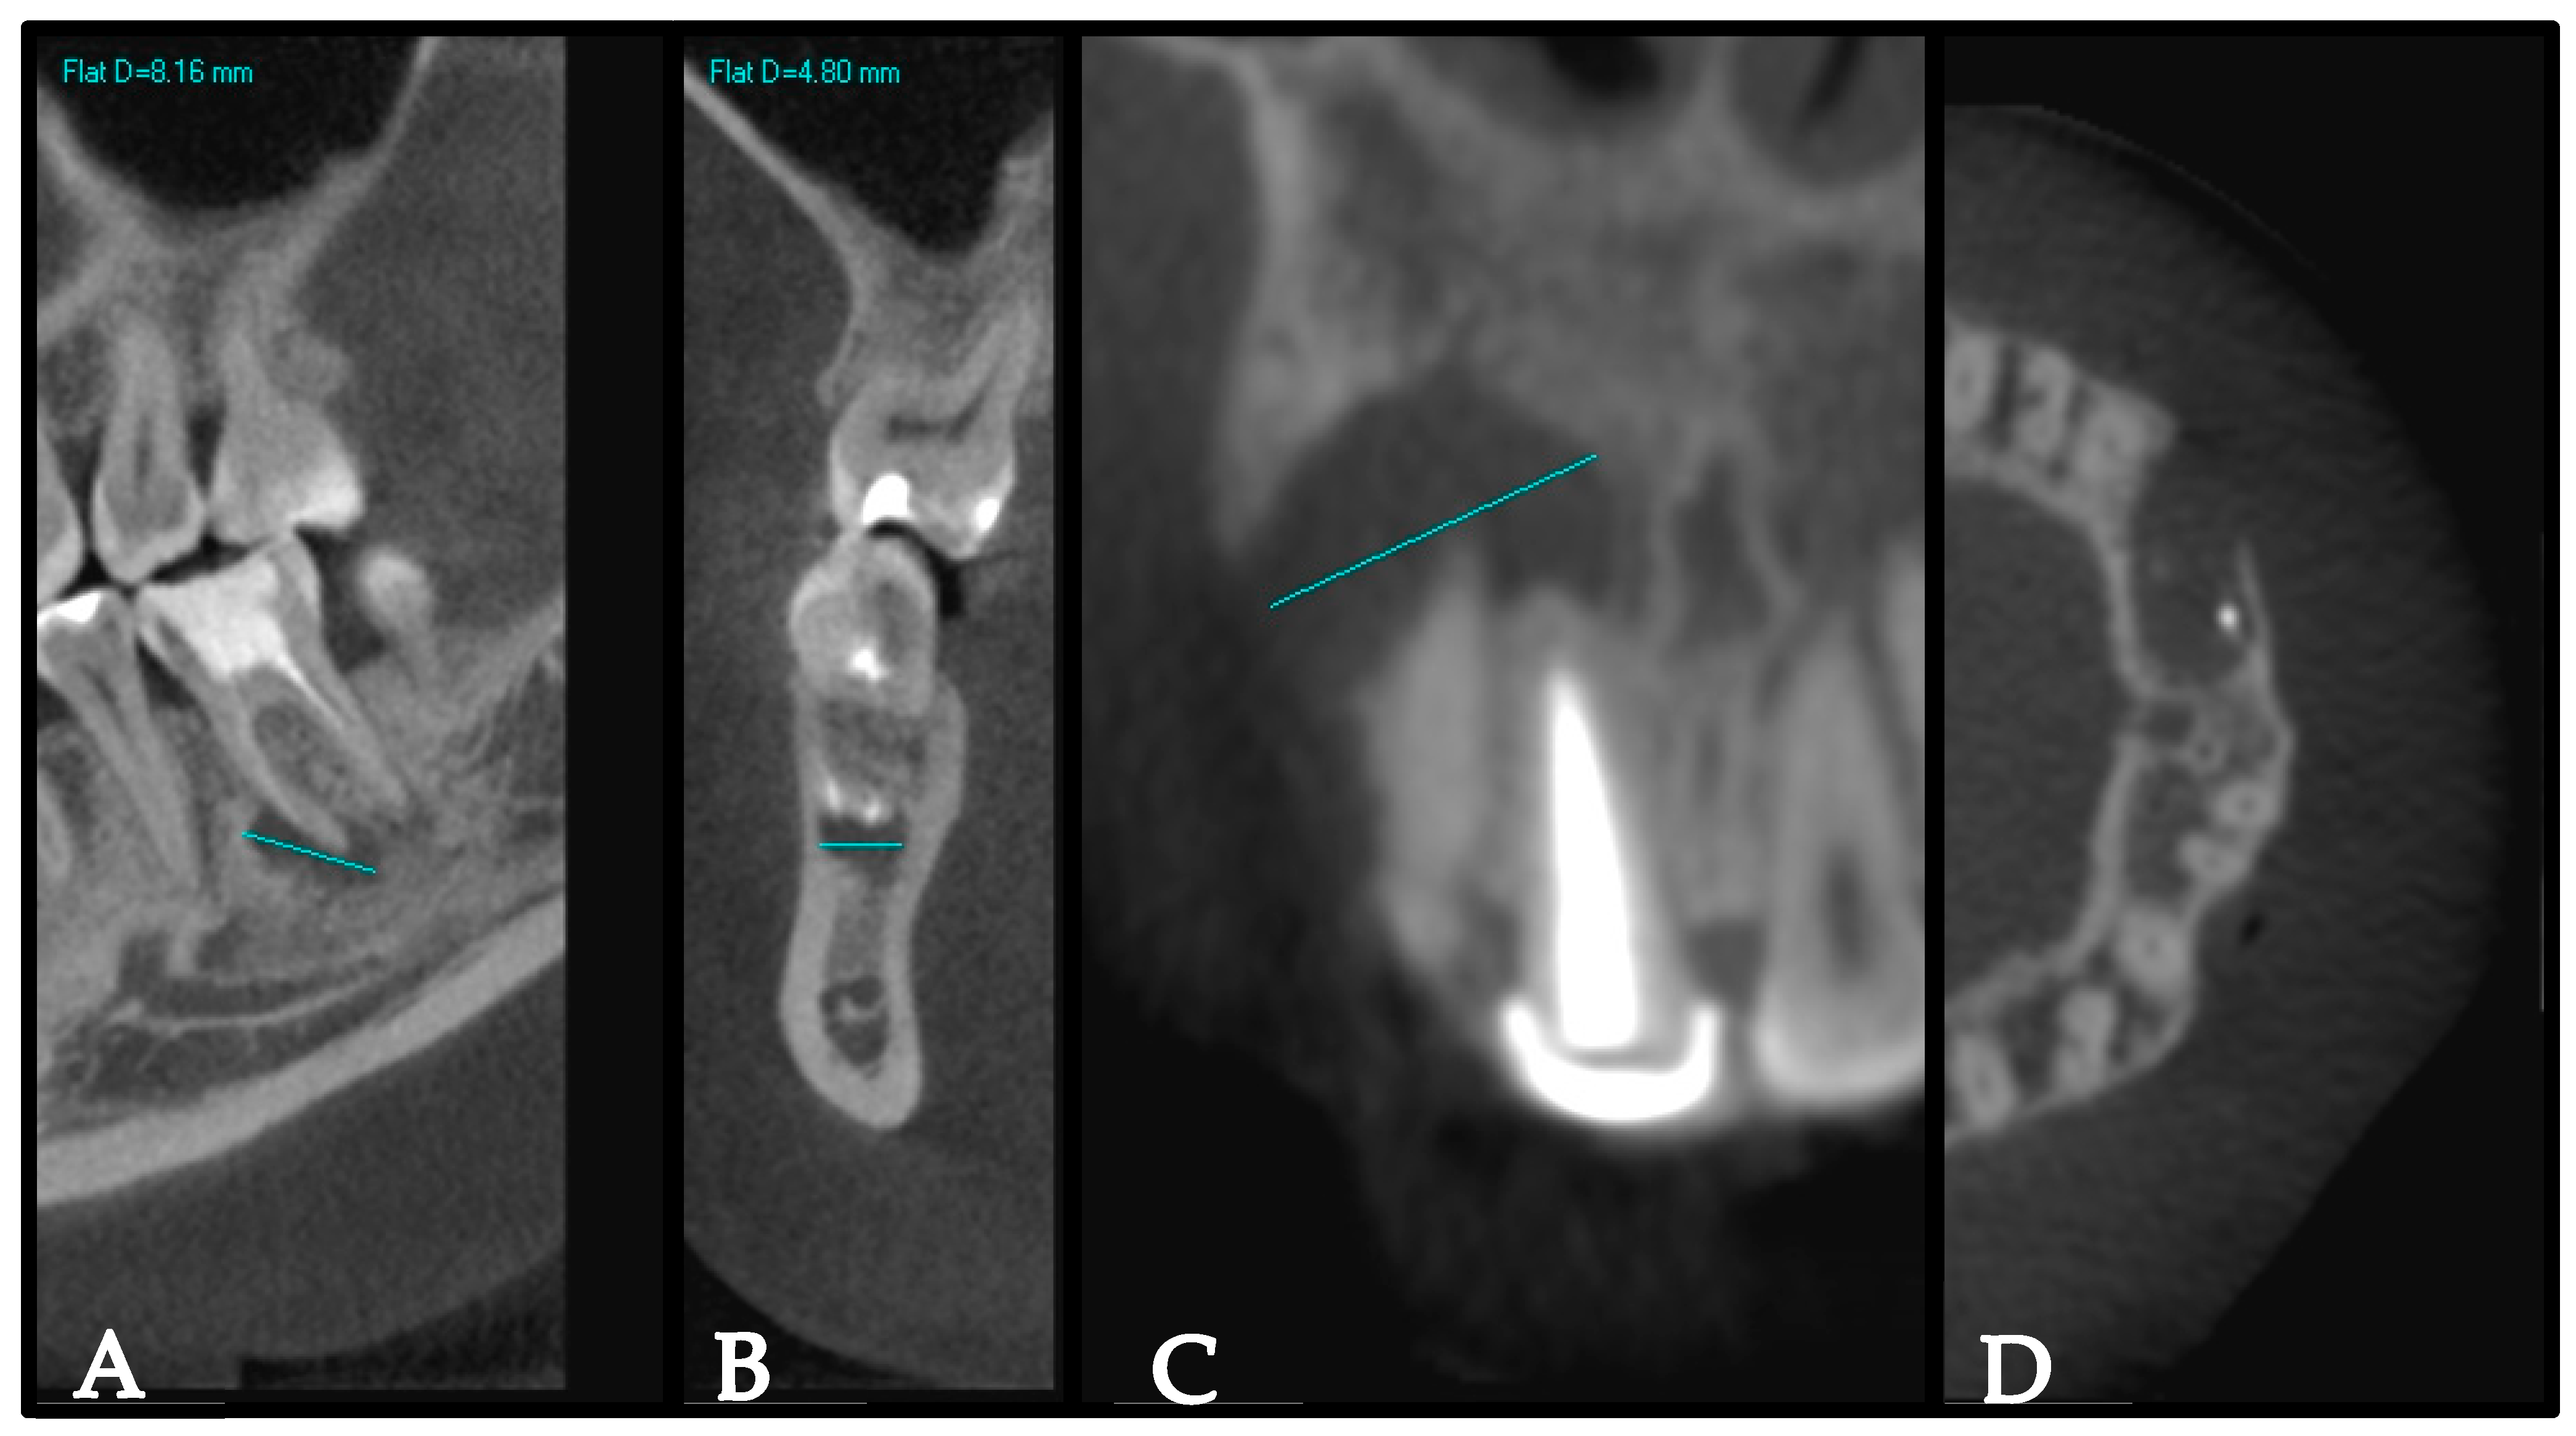

- Estrela, C.; Bueno, M.R.; Azevedo, B.C.; Azevedo, J.R.; Pecora, J.D. A new periapical index based on cone beam computed tomography. J. Endod. 2008, 34, 1325–1331. [Google Scholar] [CrossRef]